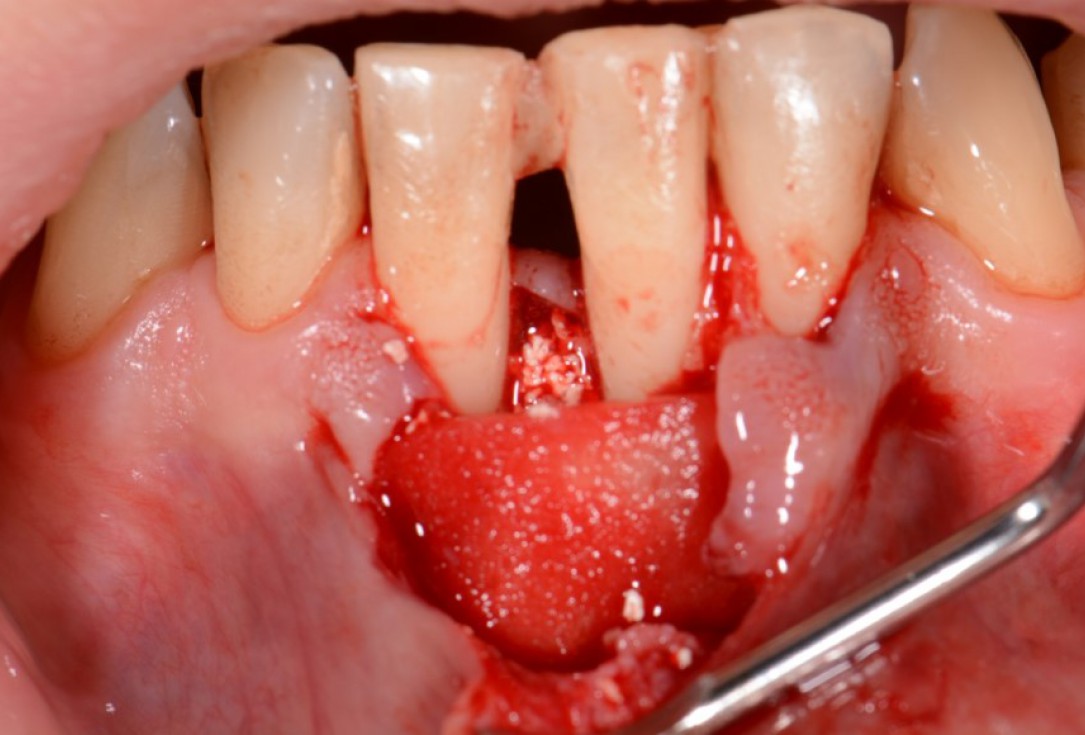

04/12 - Application of Straumann® Emdogain® to the exposed root surface.Two-wall intrabony defect treated using cerabone® and Straumann® Emdogain® - Dr. D. Rakasevic & Prof. Dr. S. Jankovic